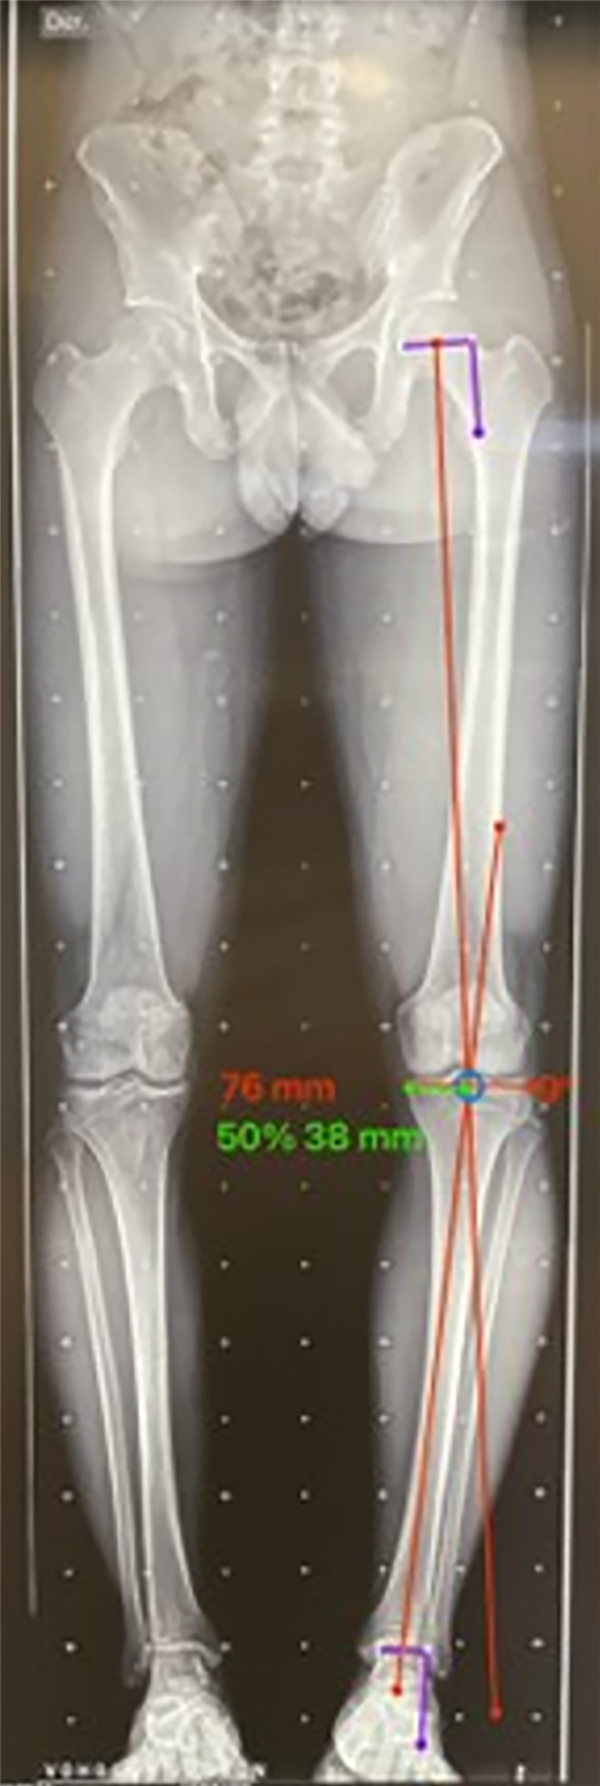

El paso 0 consiste en trazar una línea que va del centro articular de la cadera al centro articular del tobillo, recibe el nombre de “eje mecánico del miembro inferior” y el resultado fisiológico de esta medición es una línea que debe cruzar el centro articular de la rodilla con un rango de normalidad de desviación de 3 mm hacia medial o lateral.10 Al realizar la medición de la desviación, esta medida va a recibir el nombre de desviación del eje mecánico (MAD, por su nombre en inglés), según el cual, en caso de superar los 3 mm hacia medial, se trata de una deformidad en varo con un aumento de la carga en el compartimento medial de la rodilla; cuando el MAD se encuentra superior a los 3 mm laterales, es una deformidad en valgo y aumenta la carga del compartimento lateral de la rodilla21 (fig. 3).

Figura 3: Test de mal alineamiento: las líneas rojas corresponden al eje mecánico de los miembros inferiores, se marca el centro articular de la rodilla y se observa la desviación del eje mecánico o MAD derecho hacia medial de 24 mm, y en el izquierdo de 31 mm hacia medial, se evidencia una alteración de este valor con una deformidad en varo bilateral, con mayor predominio del lado izquierdo.

Figura 8: Cálculo del punto de corrección de la deformidad en paciente con artrosis: la longitud total del ancho de los platillos tibiales es 76 mm y el 62% desde medial a lateral es 47 mm, a donde va a ir la corrección y el ángulo a corregir es de 12°.

Figura 9: Cálculo del punto de corrección de la deformidad en paciente sin artrosis: se calcula al 50% para evidenciar el cambio, encontrando que la mitad es 38 mm y el ángulo de corrección disminuye a 9°. Este cambio de la indicación de la osteotomía hace que en la figura 8 amerite una doble osteotomía (DLO) y en esta sólo con osteotomía de tibia pueda ser corregida la deformidad.